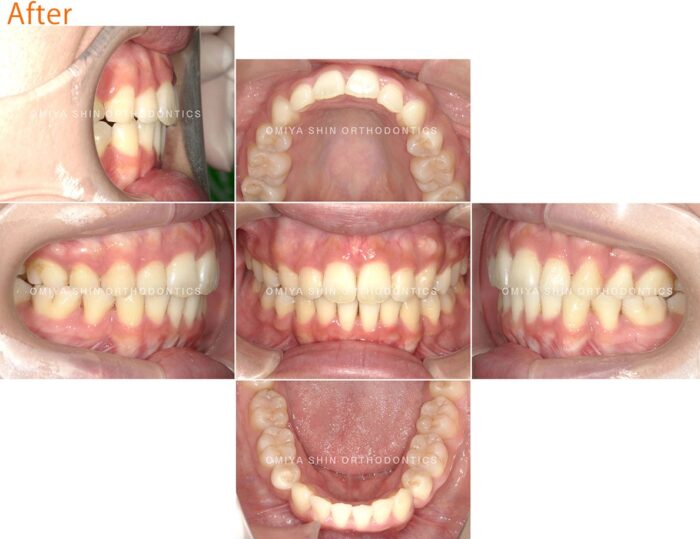

治療後

矯正治療によって歯並びを整えた結果、次のような変化が見られました。

- 前歯の突出が改善

- 口元のバランスが整う

結果として、横顔の印象にも変化が見られました。※治療の効果には個人差があります。

【症例詳細】

主訴:出っ歯が気になる

診断名:上顎前突

初診時年齢:27歳

使用装置:表側ワイヤー矯正・マウスピース矯正装置(インビザライン)

抜歯部位:上下左右第一小臼歯

治療期間:2年9ヶ月

費用:¥900,000(税込¥990,000)

リスク・副作用:痛み、歯根吸収、歯肉退縮、虫歯、後戻り